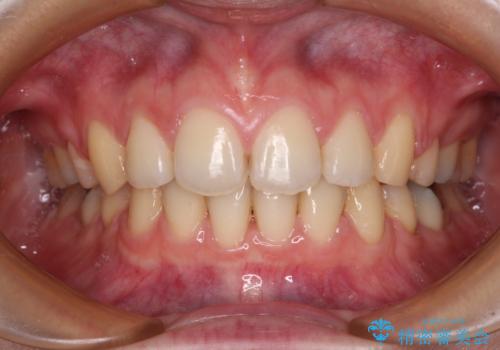

- 口元の突出感と口の閉じにくさを気にして来院された患者様です。

上下左右第一小臼歯4本を抜歯し、ワイヤー装置にて口元を引っ込めるよう矯正治療を行うこととしました。